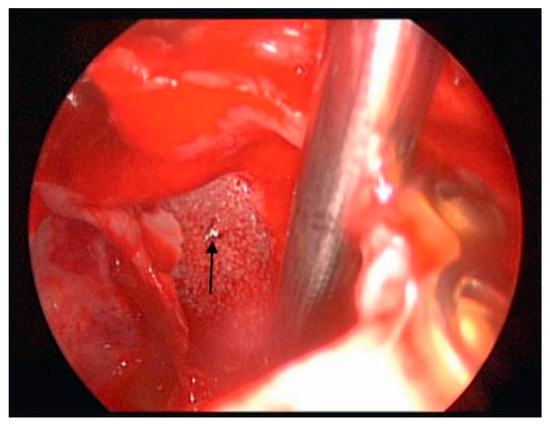

The techniques for endoscopic surgery are the same as for any open procedure, and the instrumentation for endoscopic techniques are frequently similar to open instruments. The main additions are the endoscopes, tower, camera and video monitors. The scopes today are typically Hopkins rods and come in different sizes (2.7 to 4 mm for head and neck purposes) and different angu- lations (0, 30, 45, and 70 degrees). The diameter of the glass rode can have a profound affect on the amount of light and visualization provided. The angle can also affect visualization. The camera is an industrial quality, 3-chip CCD (charge-coupled device), which is the type used for recording movie-quality videos. It is attached directly to the Hopkins rod and transmits the video signal to a tower. The tower has the printer, video equipment, light source, and monitor necessary to show the image to the surgeon. Figure 1, Figure 2 and Figure 3 show the typical instrumentation needed for any endoscopic case. For endoscopic orbital cases, the patient is into-bated and the head of the bed turned so the surgeon is on the patient’s right side. The video monitors are placed at the patient’s head for transantral orbital surgery and at the feet for endoscopic frontal sinus surgery. The gingivobuccal sulcus is then injected with local anes- thetic containing 1:100,000 epinephrine. This requires ~10 min to be maximally effective. Once the vaso-constriction is complete, a sulcus incision is made. The maxilla is stripped of periostium. Before beginning, we bend a plate for the end of the procedure. Then a 2-cm wide by 1-cm long Caldwell-Luc antrostomy is per- formed. We usually leave the bone as an osteoplastic flap for closure. Once the antrostomy is made, the intrasinus contents are cleared and decongested. After this is achieved, the nasal cavity is inspected. The roof of the sinus can now be visualized. If the patient has a trapdoor type fracture, the mucosal flaps can be raised and the bony fracture carefully opened so that the entrapped content can be replaced into the orbit. If the patient has a full-size defect, the opening should be inspected to ensure that none of the fragments are present within the orbital fat or in the inferior rectus muscle. Also of importance is the infraorbital nerve. It is extraorbital until the fissure is identified, and then it becomes intra- orbital. Care should be taken not to entrap this structure by the plating system. Figure 4, Figure 5 and Figure 6 show an antrum and the fracture in the floor.

Figure 7. Medpor with the screw placed as a handle (arrow). Medpor in place to hold periorbital fat above the floor defect.